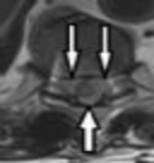

Preoperative MRI images are shown from a 67-year-old woman with neck pain, bilateral upper extremity paresthesias, progressively worsening balance, several falls, and increasing problems in both hands with dropping objects. Figure 1 is a sagittal view, Figure 2 is an axial cut at C2-3, Figure 3 is an axial cut at C5-6, and Figure 4 is an axial cut at C6-7. The patient’s motor strength is grade 4+ of 5 in the bilateral upper extremities.

What is the best next step?

4. Posterior decompression and fusion Discussion: D

The patient has degenerative changes with central and foraminal stenosis from C2-7, including spinal cord compression at C2-3, C5-6, and C6-7. Her progressively worsening balance, falls, and clumsiness are consistent with cervical spondylotic myelopathy. Given the progressive nature of the neurologic symptoms, surgery is recommended for patients with worsening

symptoms. Physical therapy potentially could provide pain relief but would not address the spinal cord compression. Cervical epidural steroid injection is not recommended because of the increased neurologic risk in the setting of substantial spinal cord compression. Given the multiple levels involved and the extension to the C2-3 level, an anterior approach would increase the risk of morbidity and pseudarthrosis compared with the posterior approach, which would allow adequate decompression of the central and foraminal stenosis.

Surgery for cervical myelopathy is performed to decompress the spinal cord, stabilize the spine, and prevent further neurologic injury. Most patients obtain considerable pain relief and some improvement in balance and clumsiness, depending on the severity of the symptoms. Complete resolution of all symptoms should not be expected.

The postoperative loss of strength in the bicep and deltoid are consistent with C5 nerve palsy, which occurs in 0% to 30% of patients following cervical decompression surgery. Commonly, symptoms occur several days postoperatively. No findings suggested infection, and infection would not lead to these symptoms. A transection of the nerve likely would have been identified during surgery, would have caused immediate symptoms, and is much less common than C5 nerve palsy. Most patients achieve near complete resolution of symptoms within 6 months without further surgical intervention, but the process can take more than 12 months in some cases. No improvement is rare. Oral or injectable steroids and revision surgery are not indicated.